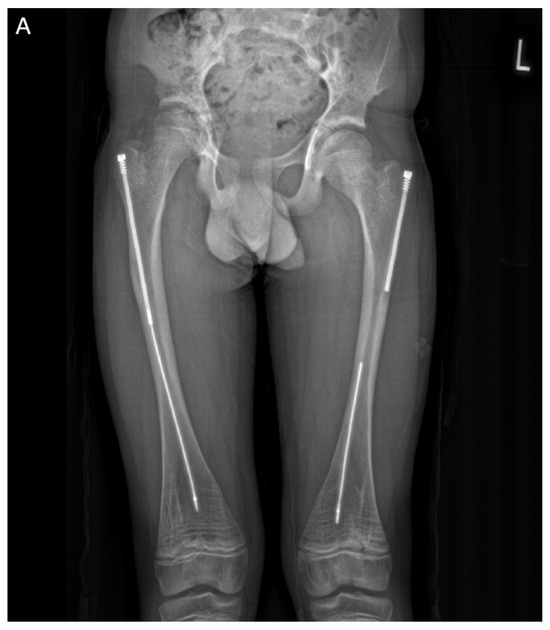

In the second case presented in this paper, a 15-year-old boy diagnosed with OI type IV, who was previously operated on 12 years ago with bilateral FD rods, presented to his regular clinic visit with pain over the left greater trochanter. This patient was ambulating without any braces or aids and was functioning very well. He did not sustain any fractures since the FD rod insertion, and full ROM of his hips was maintained. X-ray showed a completely disengaged FD rod on the left side, where the female component migrated distally and laterally across the lateral cortex. The protruding proximal part of the female component was the site of the pain and tenderness (Figure 10A). On the right side, the FD rod was almost disengaged, and a mild deformity was present anterolaterally. The X-ray demonstrates that the intramedullary canal is too narrow to accommodate an adult-sized nail. As the patient had almost reached skeletal maturity, it was decided not to use another telescoping rod but instead to use a non-telescoping SLIM nail. Because the distal male component of the existing FD rod was situated deep into the canal, making its retrieval problematic, it was decided pre-operatively to leave it in situ and insert the new rod beside it. The female component on the left side needed to be removed, and a solid SLIM rod was inserted to protect the bone (Figure 10B). Revision to a non-telescoping rod was considered for the right side as well; however, surveillance was opted for as the patient was approaching skeletal maturity. In this case, the indication for use of the SLIM nail is a near skeletally mature patient, therefore, not requiring a telescoping nail. However, the intramedullary canal was too narrow to accommodate a larger solid nail.

Figure 10.

(A)—Pre-operative X-ray. (B)—Post-revision X-ray showing installed SLIM nail in the left femur.